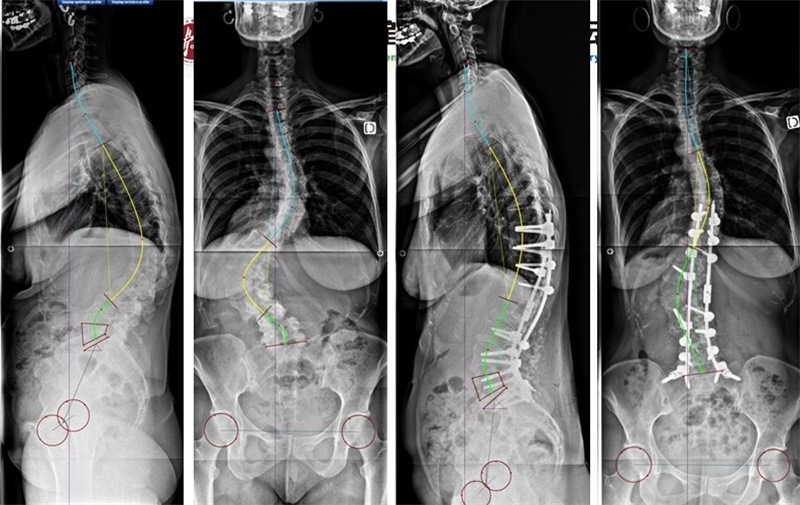

在骨盆后倾的2型患者合并平背畸形中,建议手术增加腰椎前凸将序列,将其矫形至3或4型,但是无法预测术后胸椎后凸的代偿和近端交界区后凸(PJK)的风险。

PI较大的2型患者合并平背畸形,将其矫形至3或4型

术后发生PJK

若骨盆后倾的2型患者合并整体后凸畸形时,建议在L3或L4行较大的PSO截骨,并行长节段融合,将脊柱矫正至3型或4型。

PI较大的2型患者合并整体后凸畸形,将脊柱矫正至3型或4型